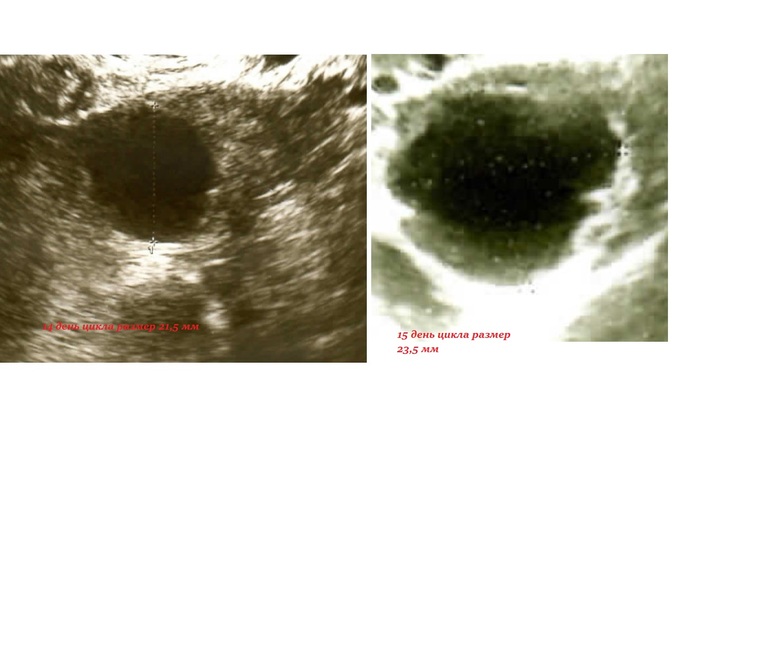

Фолликул с неровными контурами. Будет/была ли овуляция?

Девочки, вопрос, собственно, в заголовке. Кто разбирается в УЗИ - 15 ДЦ фолликул стал с неровными краями, узист подозревает что овуляции не будет и не было. Что думаете? Свой цикл 28-30 дней, на 14 и 15 ДЦ тесты на овуляцию положительные, до этого отриц. были

Скорее всего овуляция только-только произошла, в связи с этим не ровные края фолликула

Это был фолликул перед овуляцией, на 16 ДЦ уже было желтое тело